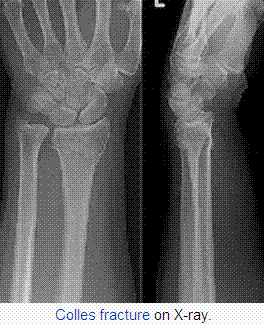

From wikipedia

A distal radius fracture is a common bone fracture of the radius in the forearm. Because of its proximity to the wrist joint, this injury is often called a wrist fracture.